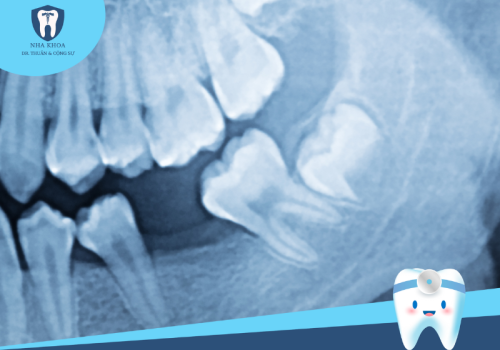

- Răng bị hư hỏng do sâu răng, mòn men răng, viêm tuỷ.

- Răng đã chữa tuỷ

Ngược lại nếu trong trường hợp răng đang thường có một số vấn đề bệnh lý và phải chữa tuỷ thì tuổi thọ của răng sẽ ngắn hơn vì tuỷ răng là nguồn sống của một chiếc răng, tuỷ bị tổn thương phải điều trị thì chắc chắn răng sẽ bị vôi hoá và dễ nứt gãy theo thời gian nhanh chóng.

Chất lượng cùi răng

Nếu bị mài cùi quá nhiều sẽ ảnh hưởng không tốt tới tuỷ làm bệnh nhân bị ê buốt, nhiều trường hợp cần phải trì hoãn việc bọc răng sứ để lấy tuỷ răng mà chất lượng chưa chắc đã tốt. Ngược lại nếu mài cùi răng ít quá sẽ làm răng sứ không đẹp mà còn dễ bị cộm khớp cắn sau này.